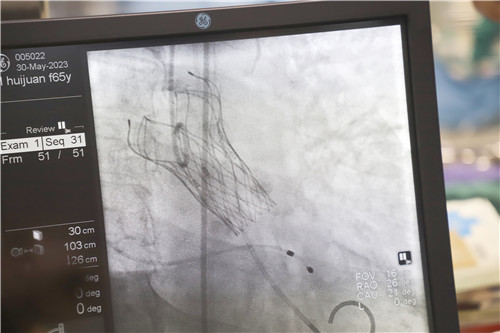

為保證創(chuàng)傷小、恢復快、并發(fā)癥可控,心血管內科聯合麻醉科、醫(yī)學影像科、超聲醫(yī)學科等多學科會診,反復溝通討論,最終決定施行TAVR手術,并征得王女士及家人的同意。該項微創(chuàng)介入技術對術者的技能操作水平和醫(yī)院的綜合救治能力要求極高,從大腿股動脈置入導管,再通過導管將人工生物心臟瓣膜輸送至已經病變狹窄的瓣膜位置,取代其瓣膜功能。

不為良相,便為良醫(yī)。石化醫(yī)院心血管內科團隊在汪念東副院長的帶領下和皖南醫(yī)學院弋磯山醫(yī)院湯圣興教授的指導下,術中利用豬尾管懸吊AL1導管增強同軸跟進,經過多學科四個小時的緊張救治,最終建立軌道成功置換瓣膜。

王女士術前測壓力階差高達110mmHg,在置換瓣膜后,壓力階差恢復到5mmHg,且無瓣周漏,在麻醉蘇醒后恢復了自主心率和自主呼吸。